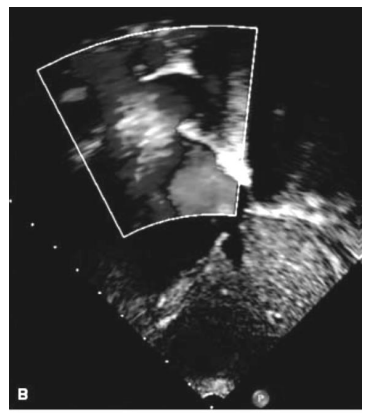

Paciente de 2 anos é levado para avaliação cardiológica após realização de ecocardiograma por sopro cardíaco. Os pais negam sintomas na criança. A respeito da patologia ilustrada no resultado do exame, assinale a alternativa correta.